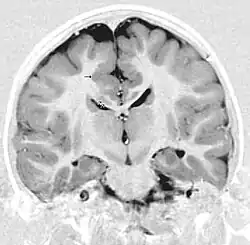

- Radiological findings (MRI) demonstrated symmetric generalized polymicrogyria with decreasing anterior-posterior gradient, most prominent in frontoparietal cortex.[5]

- Numerous gyrus on the cortex

- Small gyri and sulci

- Thin cortex

There are different tests or methods used to determine GPR56 expression or visuals of the brain to analyze the specific sections that are affected. These tests for example, using animals such as mice, RNAi, Behavioral assay, Electron microscopy, CT scan, or MRI demonstrate different results that concludes an affected BFPP patient.[15] MRI's reveal either irregularity to the cortical surface suggestive of multiple small folds or an irregular, scalloped appearance of the gray matter-white matter junction.

Neuroimaging

The diagnosis of polymicrogyria is typically made by magnetic resonance imaging (MRI) since computed tomography (CT) and other imaging methods generally do not have high enough resolution or adequate contrast to identify the small folds that define the condition. The cerebral cortex often appears abnormally thick as well because the multiple small gyri are fused, infolded, and superimposed in appearance.[5]